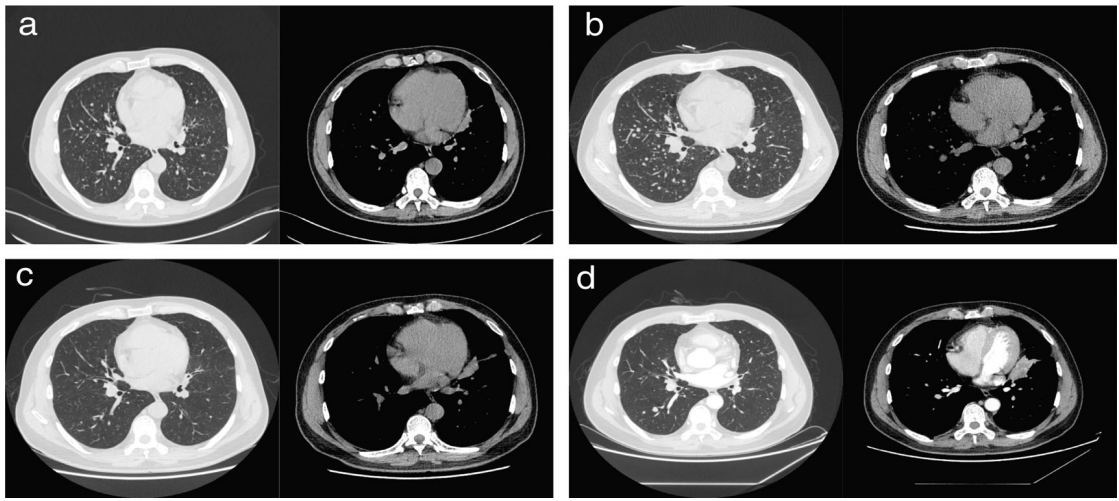

一名40岁男性,有吸烟史,于2020年1月出现进行性骶骨疼痛。磁共振成像(MRI)显示骶骨有7.7× 2.2× 5.6厘米的肿块。骶骨活检显示肺腺癌骨转移。胸部计算机断层扫描(CT)显示左上肺有一个病变,双侧肺有多个结节(图1(a))。纵隔淋巴结和骨也有多处转移。证实了肺腺癌T4N3M1(IV期)的临床分期。

图1. 胸部计算机断层扫描(CT)和后续CT图像。(a)治疗前左上肺的一处病变,伴有弥漫性双侧肺结节和纵隔淋巴结肿大;(b)尽管左上肺的病变是稳定的,但在派姆单抗加化疗两个周期后,弥漫性双侧肺结节的大小和数量有所增加;(c)派姆单抗加化疗三个周期后,双侧肺结节的大小和数量进一步减少;(d)2021年3月的胸部CT显示左上肺病变增大

患者PD-L1肿瘤比例评分(TPS)为2%(22C3)。肿瘤组织的下一代测序(NGS)显示EGFRex20ins突变(Ser768_Asp770dup,突变等位基因频率[MAF],85.16%)和TP53突变(MAF,86.09%)。从2020年6月开始患者每3周接受一次培美曲塞和卡铂联合培美单抗的一线治疗,同时接受姑息性放射治疗(30Gy/10f/2w)治疗骶骨转移瘤。经过两个周期的治疗,患者的表现有所改善,左上肺肿块稳定,但双侧弥漫性小结节的大小和数量有所增加(图1(b))。

检查了肿瘤标记物,发现血清癌胚抗原(CEA)和多糖抗原19-9(CA19-9)水平急剧下降。患者继续接受派姆单抗联合培美曲塞和卡铂治疗。第三个疗程后,胸部CT扫描显示弥漫性肺小结节完全消退,左上叶病变稳定(图1(c))。在一线治疗期间,患者无进展生存期(PFS)为9个月,疾病得到控制。2021年3月,发现左上肺的病变和肿瘤标记物增加(图1(d))。随后进行经支气管肺活检,确认肿瘤进展。肿瘤组织的NGS显示与第一次活检相同的EGFRex20ins突变。此后,从2021年3月开始患者每3周接受一次派姆单抗加多西他赛和贝伐单抗治疗 ,疾病保持稳定(图2)。该患者定期随访至2021年7月。